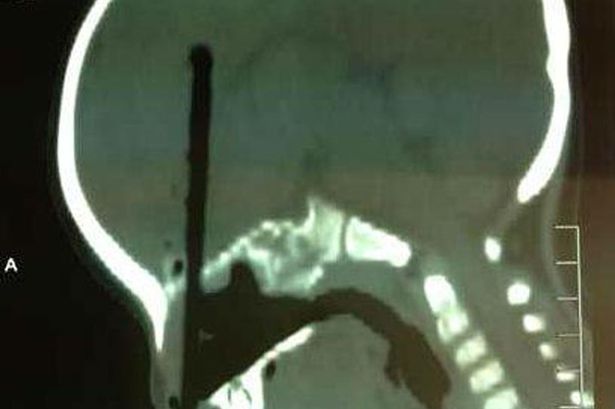

Ảnh chụp X-quang cho thấy chiếc đũa xuyên vào não cậu bé đến hơn 7cm. |